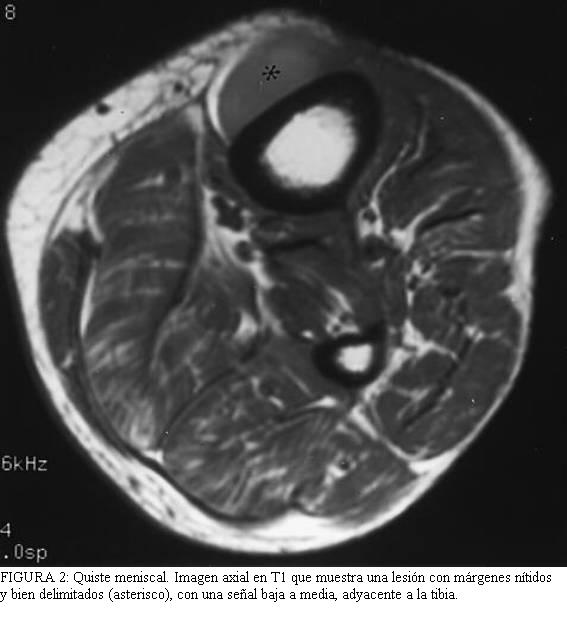

Los

más agresivas (figura 1).